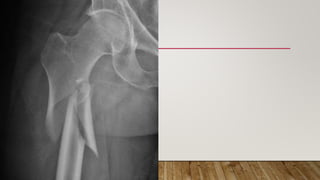

This document discusses radiology and the use of x-rays. It begins with an introduction to radiology and x-rays, noting their importance as the "father of medical investigations." It then discusses anatomy as seen on radiographs and whether x-rays are enough. The document goes on to compare gross views to radiological views, noting what each can and cannot show. It highlights important figures in the development of radiology, from x-rays to CT, MRI, and ultrasound. Specific anatomical structures visible on upper and lower limb x-rays are listed. The document concludes by discussing how pathologies appear on x-rays and the importance of clinical history and knowledge when interpreting radiological images.